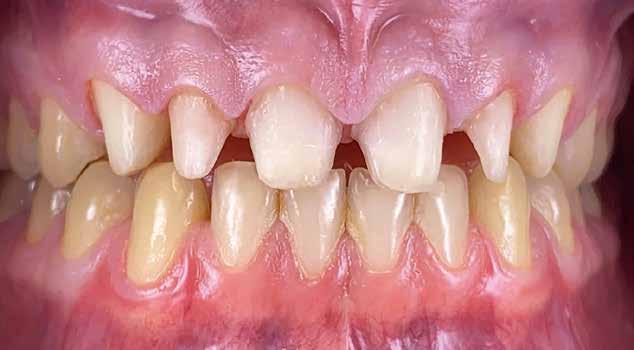

Kiindulási helyzet

A páciens látlelete a következő:

• krónikus általános parodontitis

• a 24-től terjedő parodontális fekély

• hatástalan kapcsos felső fogpótlás (1-2. képek)

Terápia

A kezelőorvos (dr. Werner Knapp, Würzburg) ennek alapján a következő terápiát javasolta:

• a 24-es fog extrakciója, illetve az 12 és 22 fogak extrakciója előrehaladott szövetveszteség okán

• szisztematikus parodontitis-terápia

• új, teleszkóp-elhorgonyzású felső fogpótlás az 16, 15, 13, 23 és 27 fogak felhasználásával (3. kép)